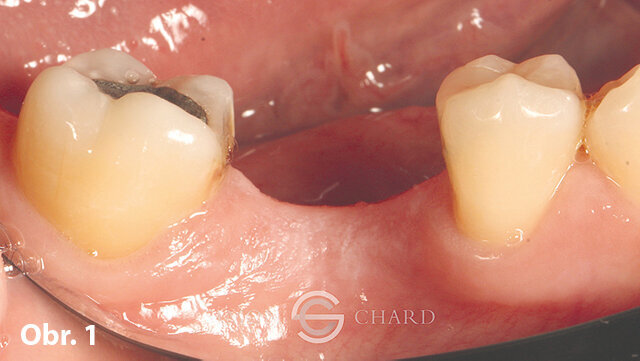

Tato případová studie pojednává o netradiční metodě zhotovení suprakonstrukce na implantát s využitím moderních výhod digitálního intraorálního skenování a ordinačního frézování. Ilustruje, jak může být korunka kotvená na implantátu vyrobena v ordinaci bez potřeby otiskování s analogy (obr. 1, 2: počáteční situace).

Po diskuzi s pacientem se v rámci možností náhrady zubu 16 rozhodl pro variantu nesenou implantátem. S pomocí operační šablony zajišťující správnou pozici pilotního vrtáku byl zaveden implantát MegaGen AnyRidge 4 × 10 mm. Za využití MegaGen fuse abutmentu a materiálu DMG Luxatemp byla následně zhotovena provizorní korunka. Poté byl z diagnostického wax-upu zhotoven silikonový klíč a dočasná korunka byla vyleštěna a vyřazena z okluze, aby bylo umožněno plné vhojení implantátu (obr. 3).